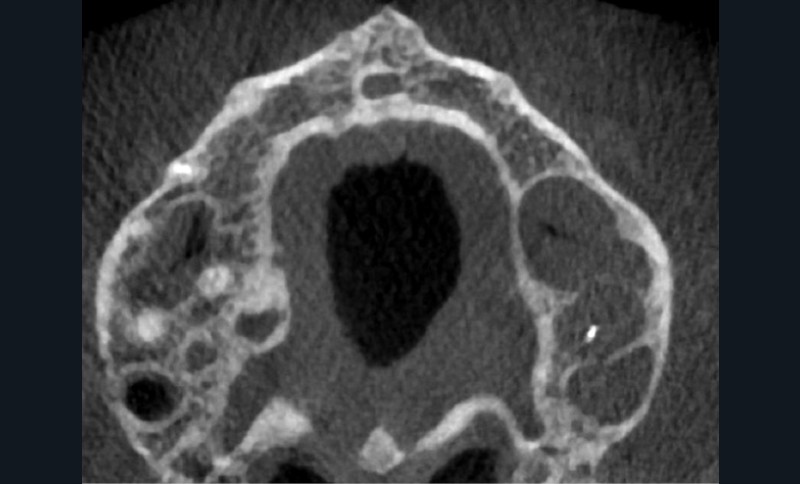

Endal, en 2011, montrait également, en utilisant le micro CT Scanner, l’insuffisance de nettoyage des isthmes inter-canalaires à nos techniques conventionnelles [19]. L’utilisation du laser Er:YAG devenait alors incontournable dans le nettoyage de ces isthmes et des zones non instrumentées (fig. 2 et 3).

Cette pénétration s’étend de la chambre pulpaire au réseau canalaire, isthmes, deltas apicaux et tubulis dentinaires. Il a été démontré que l’effet de cavitation pourrait permettre la destruction des bactéries à des profondeurs de 300 à 400 µm au sein des surfaces irradiées [20].

Si l’étude de Peters [18] nous montre que l’instrumentation laisse 35 % du volume canalaire non instrumenté, Ricucci et Siqueira montrent que la préparation physico-chimique n’élimine que partiellement les tissus nécrotiques à l’entrée des canaux latéraux, des isthmes et des ramifications apicales, en laissant des tissus enflammés et infectés, en association avec des lésions apicales [29] (fig. 4 et 5).

Fig. 4 – Coupe d’une racine mésiale de molaire mandibulaire avec deux canaux traités. Coupe à 3 mm de l’apex, coloration Brown et Brenn, technique modifiée par Taylor. Ces images montrent un isthme étroit avec une infection bactérienne, ce qui prouve l’importance de désinfecter et d’inclure l’isthme dans les traitements conventionnels et dans les rétropréparations apicales en chirurgie endodontique.

Le nettoyage des isthmes intercanalaires reste un réel problème, et semble responsable de nombreux échecs [43]. Par ailleurs, il est nécessaire d’utiliser des instruments qui évitent de propulser les débris, tant apicalement que latéralement, en obturant les entrées isthmiques avec des débris compactés.